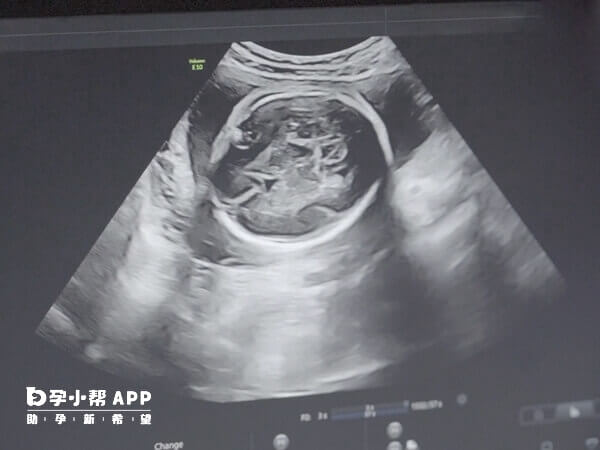

輸卵管炎症患者做一代試管嬰兒會出現宮外孕,但是這種機率比較小,如果胎兒著床比較穩定可以直接在子宮內生長,不會發生宮外孕,但是如果患者體質比較特殊,胚胎沒有在宮腔內生長,而是進入到輸卵管就會誘發宮外孕,建議患者在試管嬰兒治療後要定期到醫院進行宮腔鏡檢查,明確胎兒的生長情況。

輸卵管炎症容易導致患者輸卵管積水或者粘連,是常見不孕症,這類女性試管移植後宮外孕的機率會比普通女性要高一些。如果患者在術後生活習慣不規律,吸菸、喝酒、熬夜等等都可能造成宮外孕,另外患者宮腔環境較差,就容易在輸卵上著床導致異位妊娠。

同時輸卵管病變被認為是試管異位妊娠發生的最主要原因,輸卵管狹窄和纖毛脫落,被移入子宮的胚胎不僅可以到達輸卵管,也可以因為輸卵管病理改變阻礙其返回宮腔,導致胚胎極易種植在輸卵管形成異位妊娠,胚胎髮育與子宮內膜發育不同步,也會導致宮外孕的發生,移植數目過多,有過盆腔手術史,子宮內膜異位症,生殖道畸形等,會增加做試管後出現宮外孕的機率。